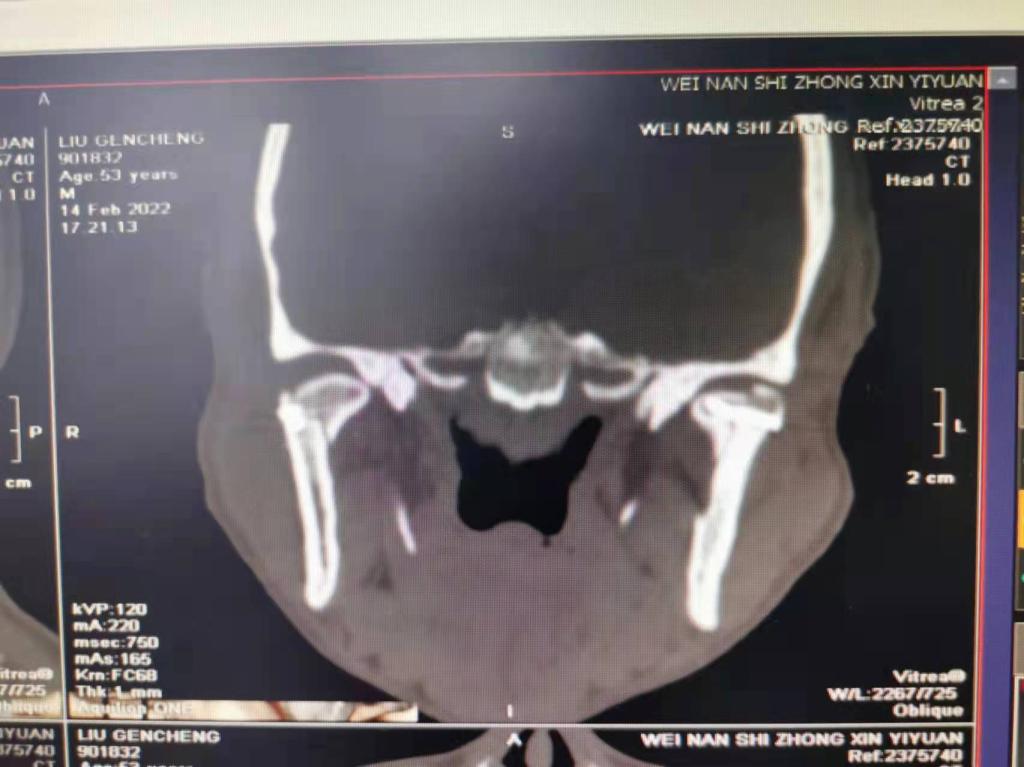

据了解,53岁的患者刘先生在1月25日当天走路不慎摔倒致下颌损伤,造成颏部软组织裂伤和张口困难,前往当地卫生院进行颏部裂伤清创缝合术。术后辗转到乐鱼手机站入口口腔科门诊就诊,并进行颌面部CT检查提示为下颌颏部正中和双侧髁状突骨折,双侧下颌升支高度不一致,右侧较左侧变短1cm,张口重度困难,咬合关系错乱。刘先生因考虑在春节过后再入院治疗,于2月8日再次前来口腔科以“下颌骨骨折”收治人院。

口腔科主治医师蔺非非为患者入院后进行完善术前常规检查和颌间牵引恢复咬合关系。科主任李瑞春结合患者实际病情和检查结果认为,患者的髁突骨折在下颌骨骨折中所占比例较高,约为17.0%-36.3%。髁突骨折时,耳前区有明显的疼痛,局部肿胀、压痛。通过手指深入外耳道或在髁突部触诊,如张口时髁突运动消失,可能有骨折段移位。双侧低位骨折时,2个髁突均被翼外肌拉向前内方,双侧下颌支被拉向上方,可出现后牙早接触,前牙开秴。髁状突骨折易引起下颌后缩,张口困难,咬合关系错乱,关节强直等并发症。考虑患者系陈旧性骨折应尽早实施手术,避免骨折导致的张口困难、关节强直等并发症。因患者已经错过最佳治疗时期,决定尽快为患者进行手术治疗。

科主任李瑞春和主治医师蔺非非经过缜密的术前讨论和充分评估,手术在全身麻醉下进行,术中克服术野狭小操作不便困难,将下颌骨骨折完好对位,顺利地完成了"双侧髁状突和下颌颏部正中骨折切开复位内固定术"。术后检查患者面部对称,双侧下颌升支高度一致,咬合关系已恢复。